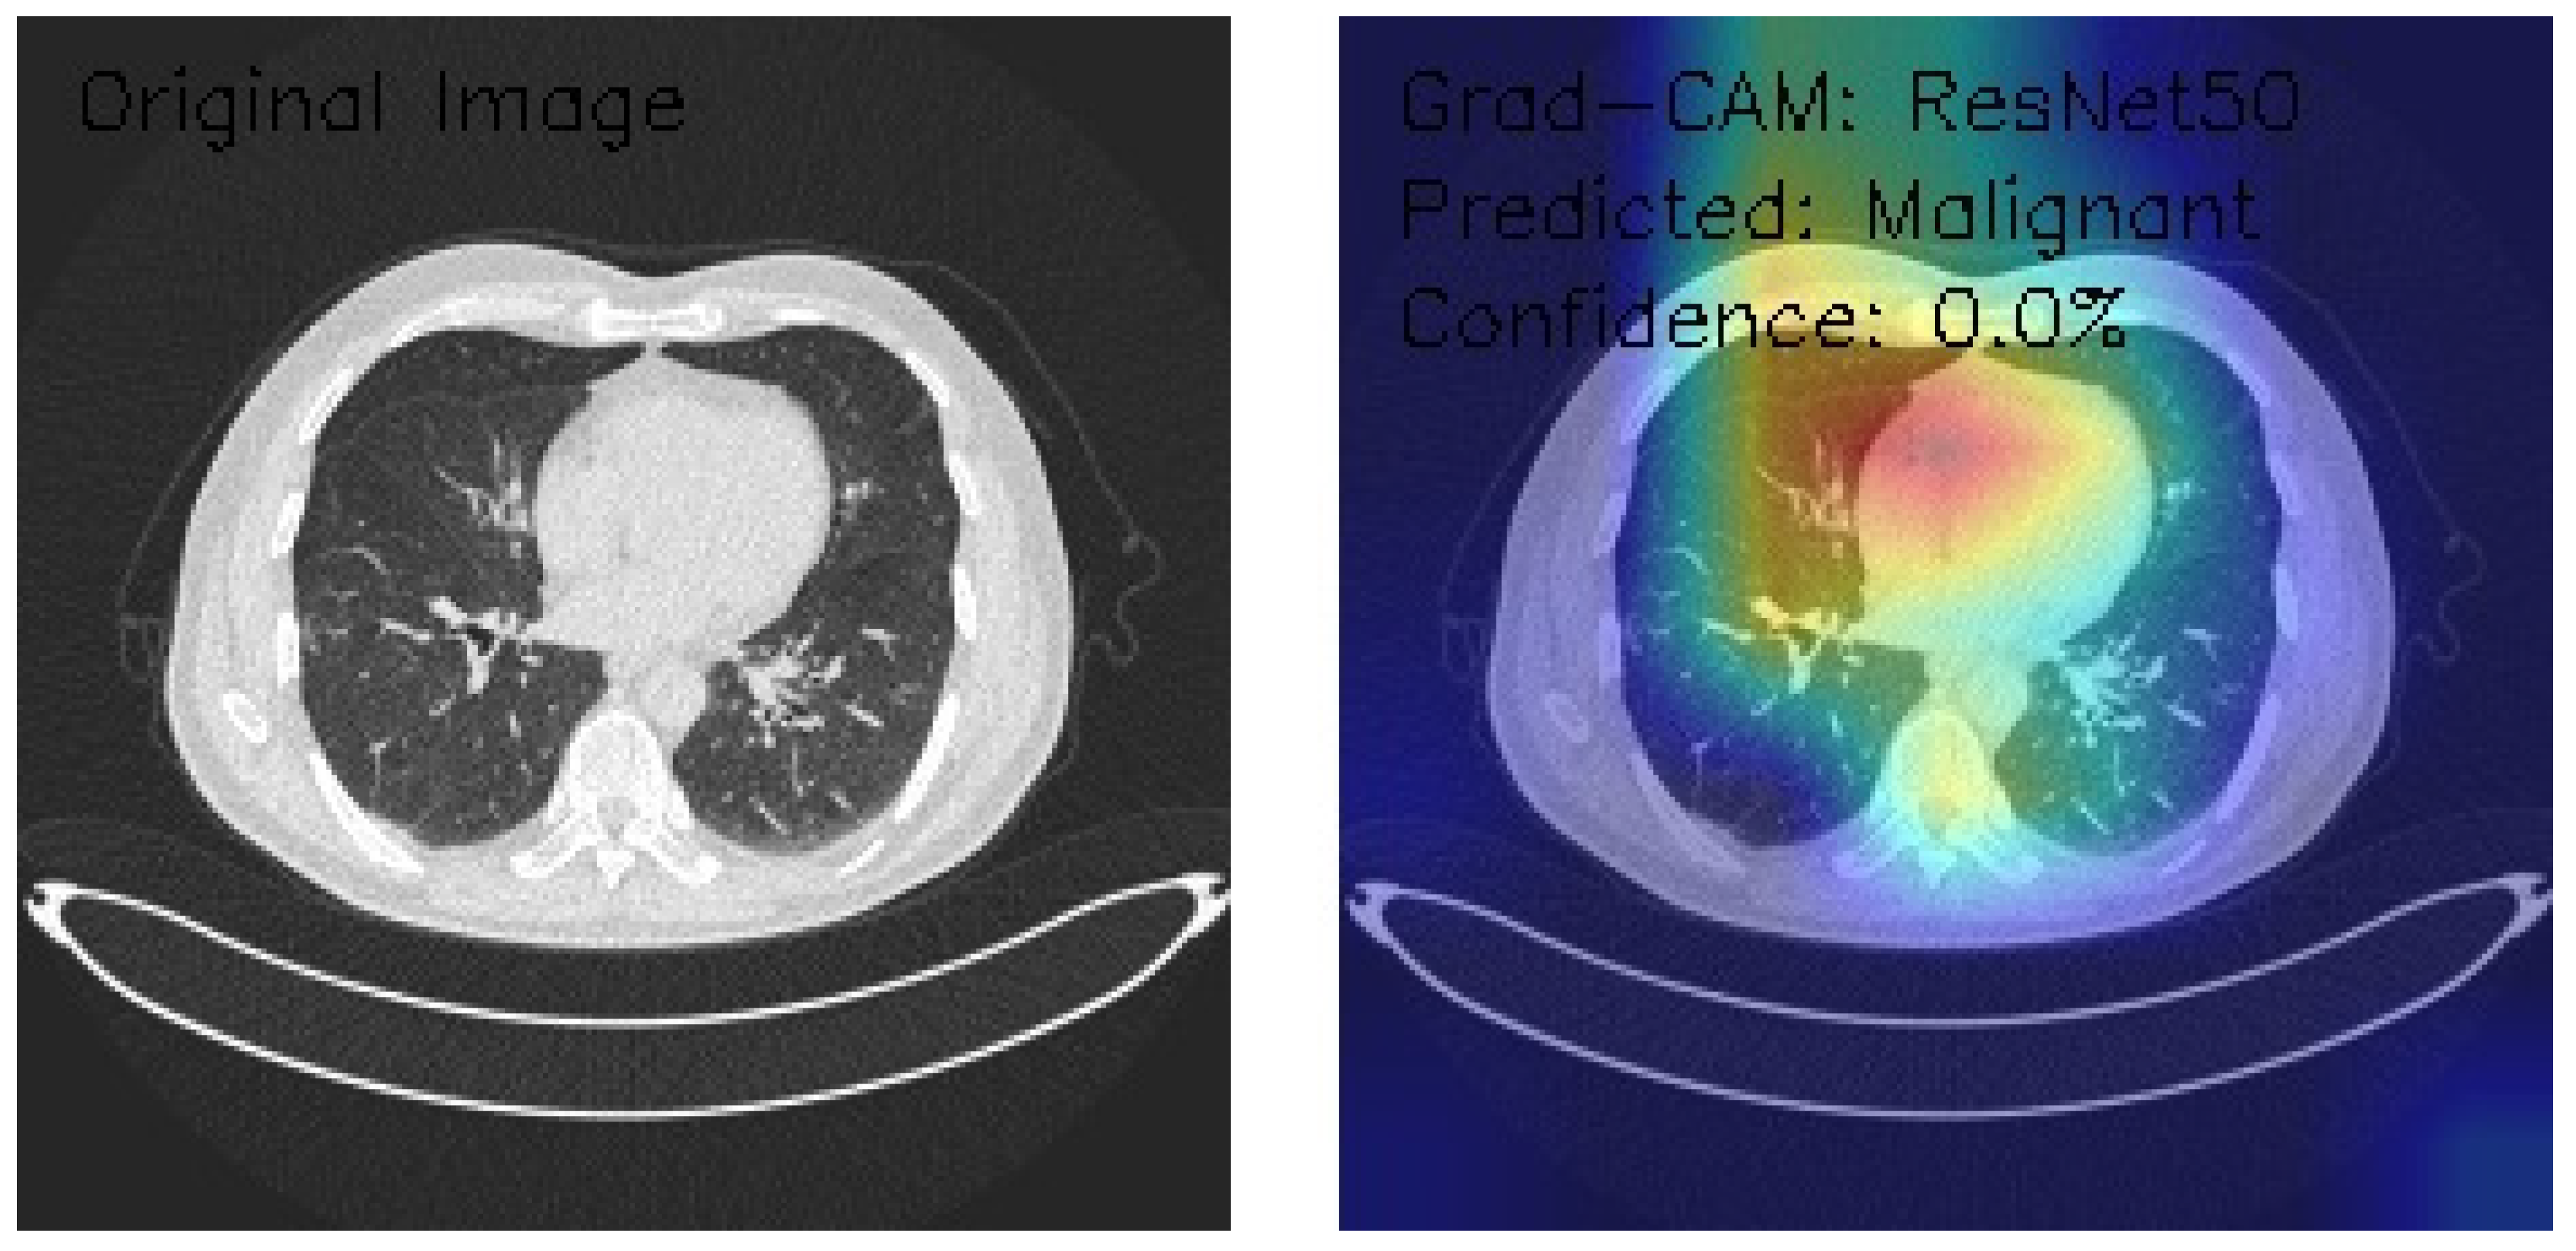

ResNet50 Deep Learning Model

The three axial chest CT images were analyzed using a state-of-the-art ResNet50 deep learning model, a widely recognized convolutional neural network architecture known for its robust performance in image classification tasks. Grad-CAM visualization was employed to gain insights into the model’s decision-making process. This technique provides a detailed heatmap overlay on the original images, highlighting the regions of interest that contributed most significantly to the classification decisions. This combined approach enables accurate classification and offers interpretability, ensuring that the underlying rationale for the model’s predictions can be understood and validated in a clinical context.

Figure 8 shows an image of distinct parenchymal patterns, particularly in the central and peripheral regions. The Grad-CAM heatmap demonstrates strong activation in the central mediastinal region, extending into the right lung field. Notably, this was classified as Malignant with 0.0% confidence, representing a shift in classification despite the low confidence score.

Figure 8.

Grad-CAM visualization using ResNet50 for lung CT scan with benign prediction. (Source: author’s analysis from data, 2024).

This analysis evaluates the application of ResNet50 with Grad-CAM visualization on three axial chest CT images, focusing on the model’s regions of interest and classification confidence. Grad-CAM heatmaps highlight consistent activation in central thoracic and lung structures, with bilateral asymmetry and variable peripheral attention. Image classifications include two Benign (Images 1 and 2) and one Malignant (Image 3), all with 0.0% confidence, indicating significant uncertainty in the model’s predictions. These results reveal model calibration and reliability issues despite its ability to identify relevant anatomical features. To enhance clinical applicability, recommendations include recalibrating the confidence scoring system, expanding the training dataset, incorporating ensemble methods, and validating results with expert radiologists. This analysis underscores the need to refine the model further to improve its diagnostic reliability and confidence.